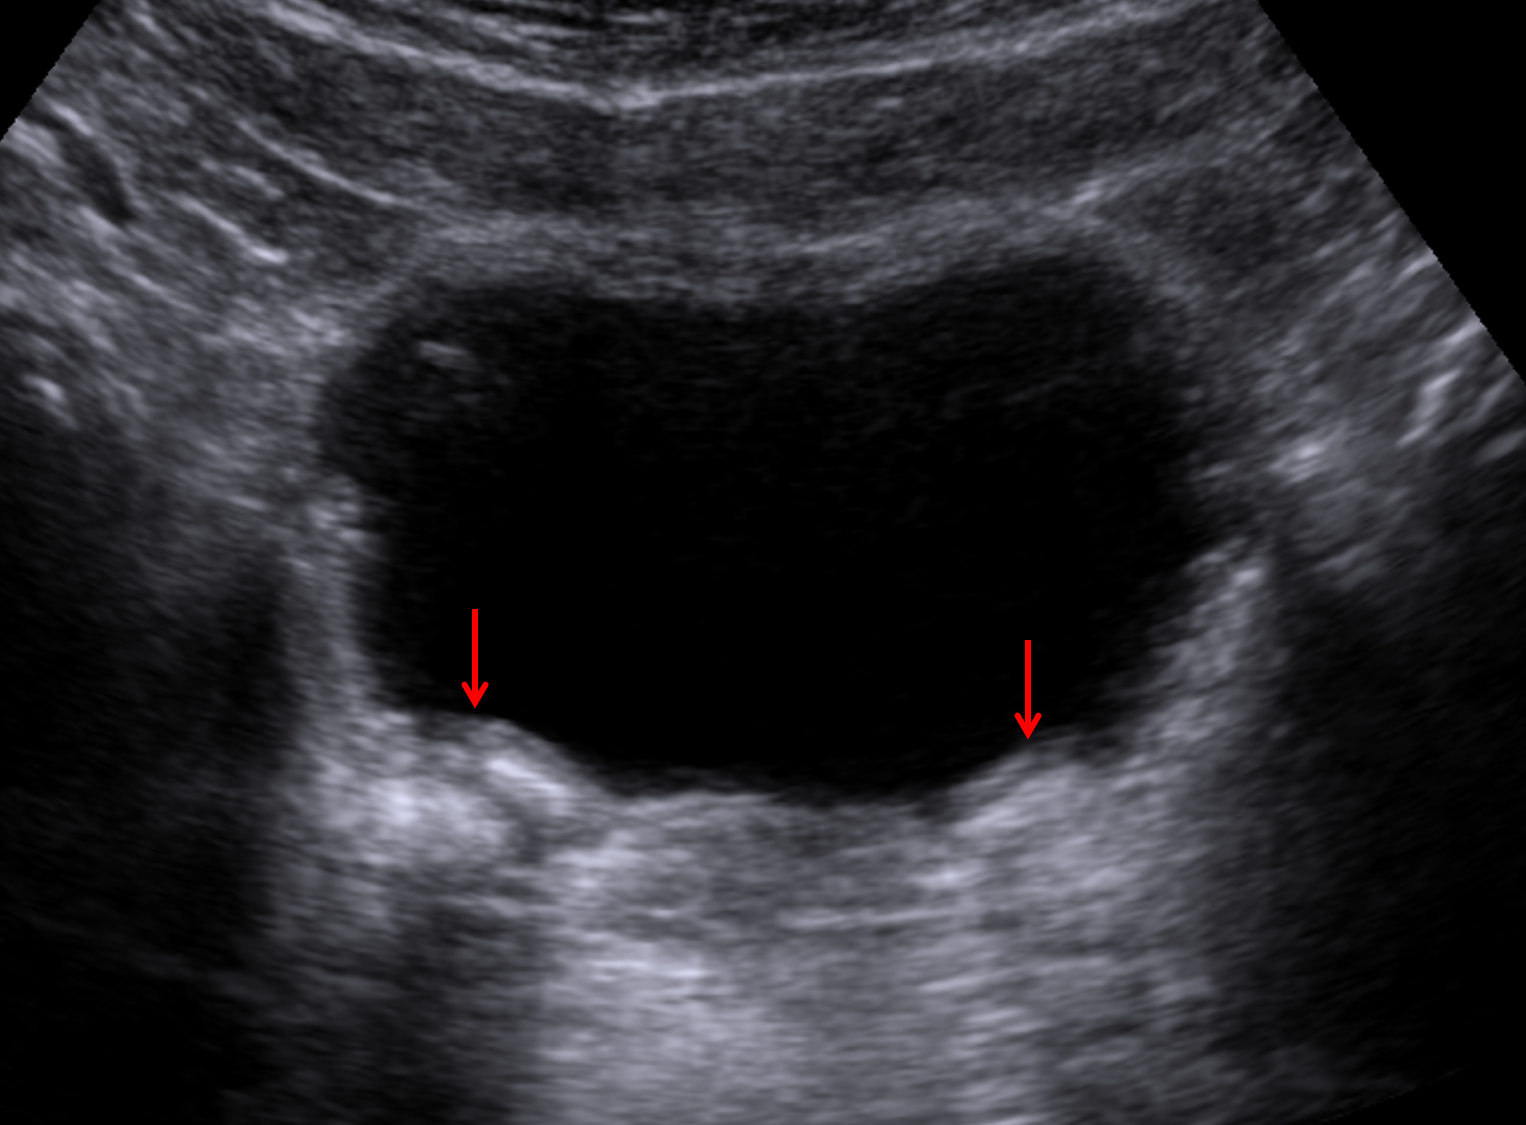

Deflux mounds

Incidental note is made of bilateral calcified bulking material at the ureterovesicular junctions related to prior treatment of vesicoureteral reflux.